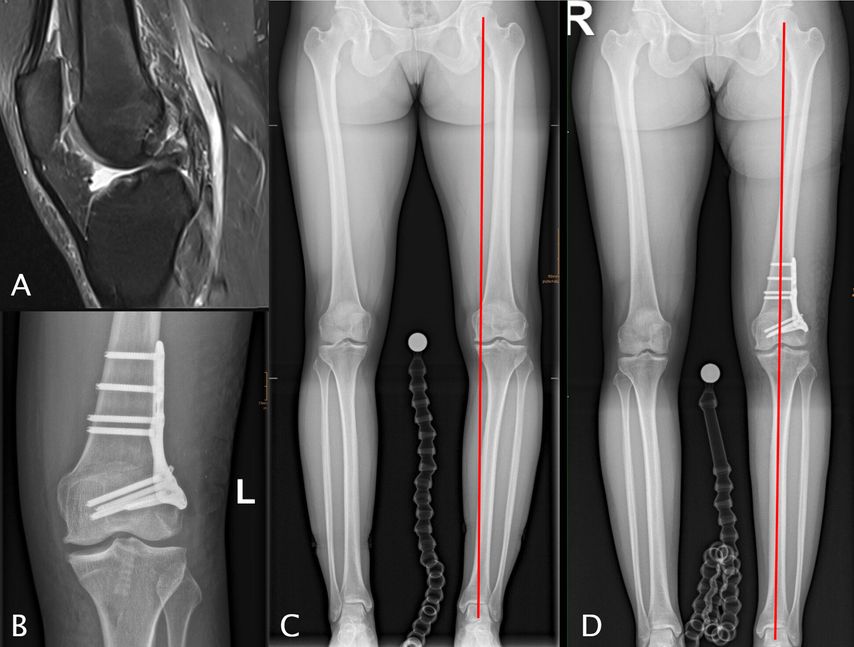

Abb. 2: 33-jährige ehemalige Leichtathletin mit einer primären VKB-Ruptur (A), deutliche Chondropathie im medialen Kompartiment, Varusfehlstellung von 9° primär aus dem distalen Femur resultierend (LDFA 92° [C]), behandelt mit einer einzeitigen CW-DFO und VKB-Plastik (4-Strang-Semitendinosus-Graft)

Abb. 3: 33-jährige weibliche Patientin mit zweifacher VKB-Reruptur (A) mit einem erhöhten tibialen Slope von 15° (B) und einer Valgusfehlstellung von 3° (C), behandelt mit einer einzeitigen Revision mitipsilateralem Quadricepssehnengraft und einer varisierenden Slope-reduzierenden HTO (D, E, F)